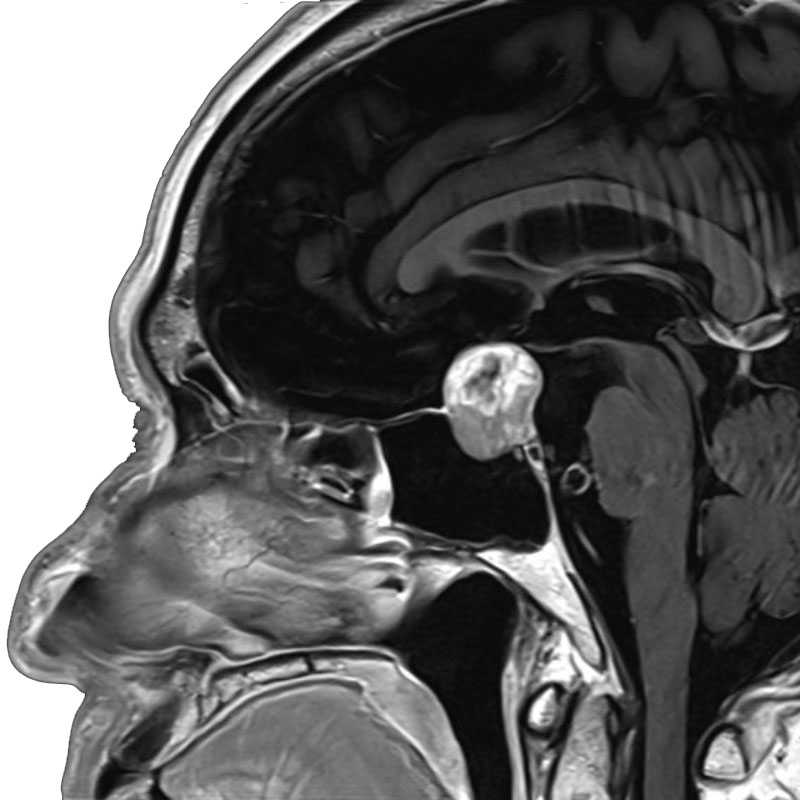

脳室内腫瘍

摘出術

北野/濵田